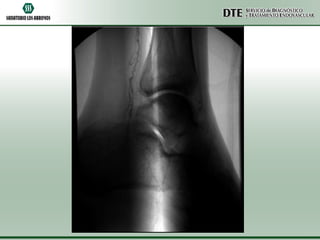

Angio RMI MMII

•El eje arterial del miembro inferior derecho no presenta

alteraciones. Se observa permeable en toda su extensión, de buen

calibre y con señal de RM conservada.

•Se observan alteraciones en el eje arterial del miembro inferior

izquierdo. Se destaca una obstrucción severa en la arteria poplítea

con ausencia del flujo distal.

•En las imágenes axiales que ponderan líquido se observa un edema

de la pared arterial y del tejido graso periarterial a nivel del hueco

poplíteo.

•No se definen dilataciones aneurismáticas ni procesos sólidos en

partes blandas ni en el hueso.

•A nivel del hueco poplíteo se observa circulación colateral.

•No se observa flujo en el origen del tronco arterial tibio-peroneo ni

el origen de la arteria tibial anterior.

•Los vasos antes mencionados se repermeabilizan por circulación

colateral.

Angio RMI

•CONCLUSIÓN:

•ANGIORRESONANCIA MAGNÉTICA DE MIEMBROS INFERIORES

QUE MUESTRA UNA OBSTRUCCION SEVERA Y STOP AL FLUJO EN

LA ARTERIA POPLITEA IZQUIERDA, CON REAPERTURA DE

CIRCULACION COLATERAL QUE RELLENAN LAS ARTERIAS

INFRAPATELARES. A NIVEL DEL HUECO POPLITEO SE OBSERVA

EDEMA INFLAMATORIO EN LOS TEJIDOS BLANDOS DE LA PARED

ARTERIAL Y DEL TEJIDO GRASO QUE LA RODEA.

•NO SE DEFINE ESTENOSIS EN EL EJE ARTERIAL DERECHO.

•El eje arterialdel miembro inferior derecho no presenta alteraciones. Se observa permeable en toda su extensión, de buen calibre y con señal de RM conservada. •Se observan alteraciones en el eje arterial del miembro inferior izquierdo. Se destaca una obstrucción severa en la arteria poplítea con ausencia del flujo distal. •En las imágenes axiales que ponderan líquido se observa un edema de la pared arterial y del tejido graso periarterial a nivel del hueco poplíteo. •No se definen dilataciones aneurismáticas ni procesos sólidos en partes blandas ni en el hueso. •A nivel del hueco poplíteo se observa circulación colateral. •No se observa flujo en el origen del tronco arterial tibio-peroneo ni el origen de la arteria tibial anterior. •Los vasos antes mencionados se repermeabilizan por circulación colateral.

Angio RMI •CONCLUSIÓN: •ANGIORRESONANCIA MAGNÉTICADE MIEMBROS INFERIORES QUE MUESTRA UNA OBSTRUCCION SEVERA Y STOP AL FLUJO EN LA ARTERIA POPLITEA IZQUIERDA, CON REAPERTURA DE CIRCULACION COLATERAL QUE RELLENAN LAS ARTERIAS INFRAPATELARES. A NIVEL DEL HUECO POPLITEO SE OBSERVA EDEMA INFLAMATORIO EN LOS TEJIDOS BLANDOS DE LA PARED ARTERIAL Y DEL TEJIDO GRASO QUE LA RODEA. •NO SE DEFINE ESTENOSIS EN EL EJE ARTERIAL DERECHO.